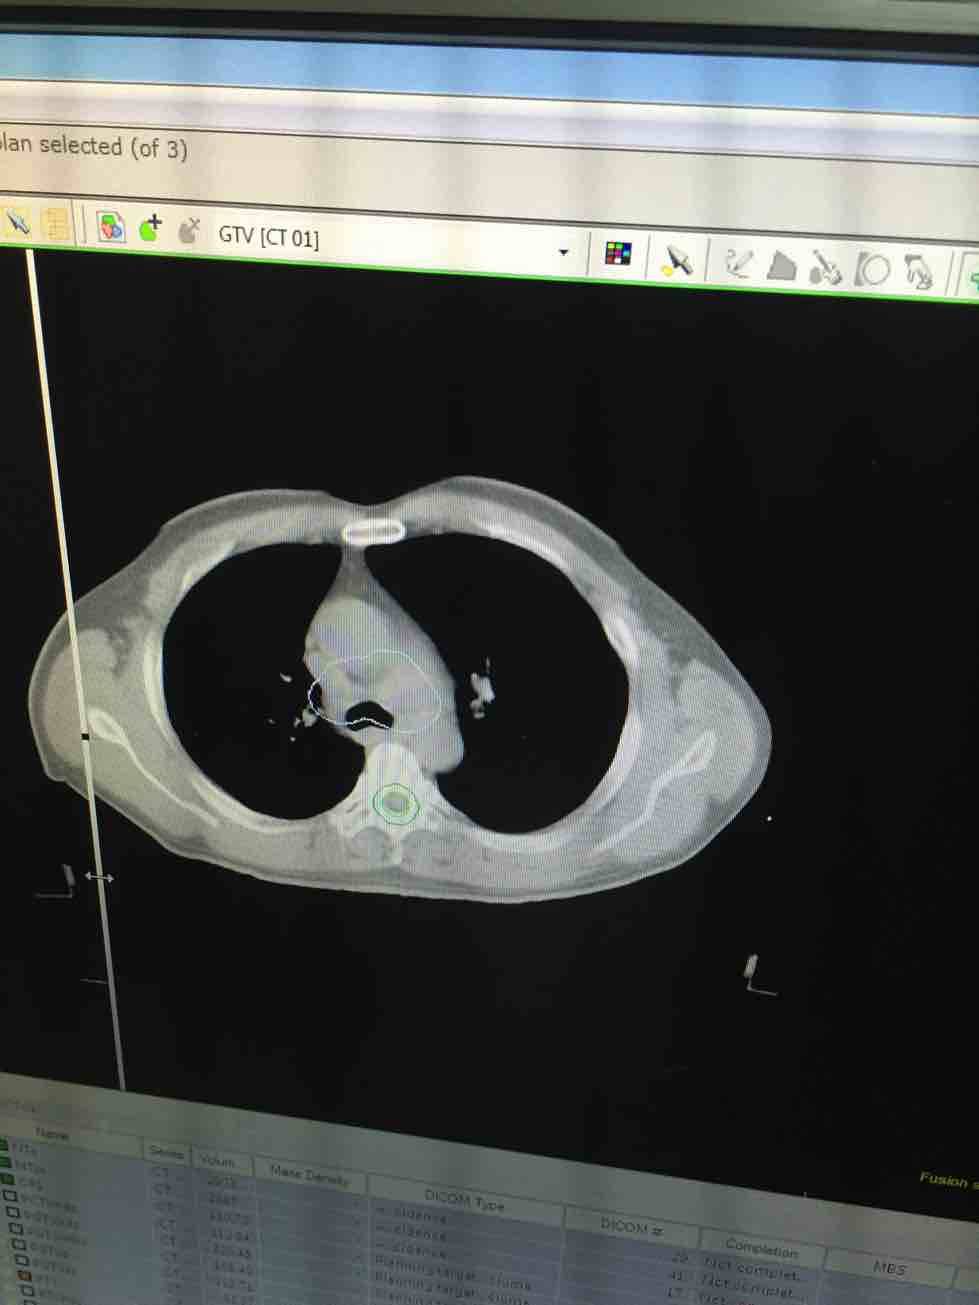

爸爸5月3日检查出小细胞肺癌局限期,马上进入化疗两次后肿瘤缩小一半,四次后肿瘤没有变化,马上转入放射科进行了25次放疗,放疗结束后医生说效果很明显,在医生电脑上拍的放疗前后的ct片对比,当时很高兴,放疗的效果真的很好!回老家休养了半个月马上进入肿瘤科准备做第五次化疗!这几天检查,等待周一评估!放疗效果那么好,不知道为什么这次的ct检查结果肿瘤比8月份的时候又大了!又进入了迷茫!下一步到底该怎么办?洛铂 依托泊苷 无效!应该换什么药更好一些?

这两张片不是同一个部位,没可比性,

你发的片子未见肿瘤病灶啊